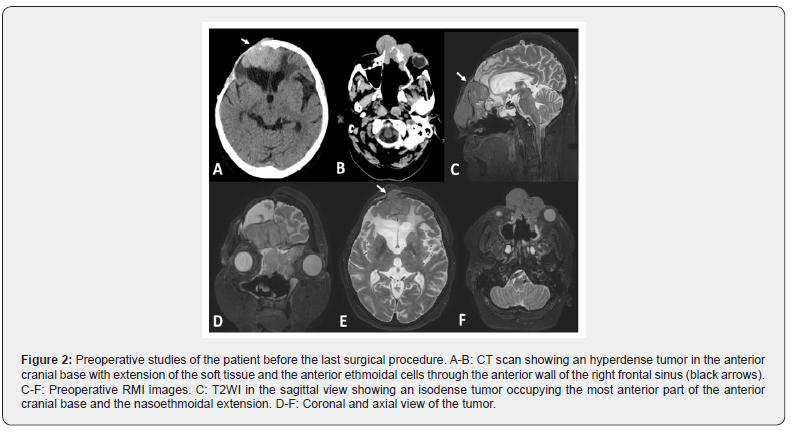

A 57-years-old female caucasian patient was referred to our institution with a previous history hypertension and a right frontal craniotomy for a World Health Organization WHO grade I meningioma with 70% removal of the lesion. Four months after she started with facial deformity, and right ocular proptosis. The CT scan showed tumor regrooving and a second frontal craniotomy was performed with a 95% resection of the tumor. The biopsy confirmed a clear cell meningioma (WHO grade II). She received adjuvant treatment with Conformal Radiotherapy (30 sessions) and Nimotuzumab (33 doses). Seven months after was treated surgically for a bone flap osteomyelitis with removal of the bone flap. Eight months after she was referred to our institution with left nasal obstruction left nasal deformity bifrontal headache, anosmia, right ocular pain and bilateral visual loss. There were not cervical lymph nodes associated. The rhinoscopy showed a left nasal tumor surrounded by normal mucosa reaching the nasal septum. The tumor sample was revised and the anatomopathological study reported an esthesioneuroblastoma. The initial laboratory findings were normal. CT revealed a not well-circumscribed isodose tumor with avid contrast enhancement and some necrotic zones in the right ethmoid and frontal sinuses, extended into the soft tissue and anterior cranial base invasion. An endonasal endoscopic transcribiform approach was performed with a partial removal of the lesion. Few weeks after the patient started again with frontobasal soft tissue growing and frontal headache (Figure 1, A-B). CT and RMI scans showed regrowing of the tumor (Figure 1, A-F).

The definitive anatomopathological study showed a meningothelial meningioma (WHO grade I) with Ki-67 higher than 4% and positivity to synaptophysin protein (Figure 1, C-E). Because of the large size of the tumor mass extending into the ethmoid-sphenoidal complex, a combined simultaneous endonasal endoscopic approach-transcraneal approach through bilateral frontal craniotomy was performed. A 0-degree straight and 30-degree endoscopes 4 mm in diameter and 18 cm in length (Karl Storz Endoscopy, Tuttlingen, Germany) were used during the nasal step. A digital endoscopic HD video camera and a full High Definition (HD) flat monitor and a 300 W Xenon light source were used during the procedures. Ceftriaxone was administered via the intravenous route within 1 hour before surgery (1.5 g) and continued for 5 post-operatively (1.5 g twice a day) until nasal packing (Foley balloon) were removed. After orotracheal intubation under general anesthesia, the patient was placed supine with head fixed in the three-point Mayfield-Kees skeletal headrest and turned 10 ̊ - 15 ̊ on the horizontal plane, towards the surgeon. The head was extended 20 degrees to facilitate the anterior cranial base exposure during the endonasal approach and the frontal lobe retraction during the transcranial approach. The nasoethmoidal tumor was removed in a piecemeal fashion. After that, a wide sphenoidotomy was performing in order to expose the postero-inferior margin of the dissection and to use both optocarotid recess as landmarks. A frontotemporal incision and craniotomy was performed. A secondary incision was made in the left naso-orbital region in order to remove the facial component of the tumor. One surgeon dissected the tumor from the inferior (endoscopic) view while a second surgeon dissected the tumor from an intracranial view with a microscope. Thus, four hands, two surgeon’s technique was done (Figure 2).